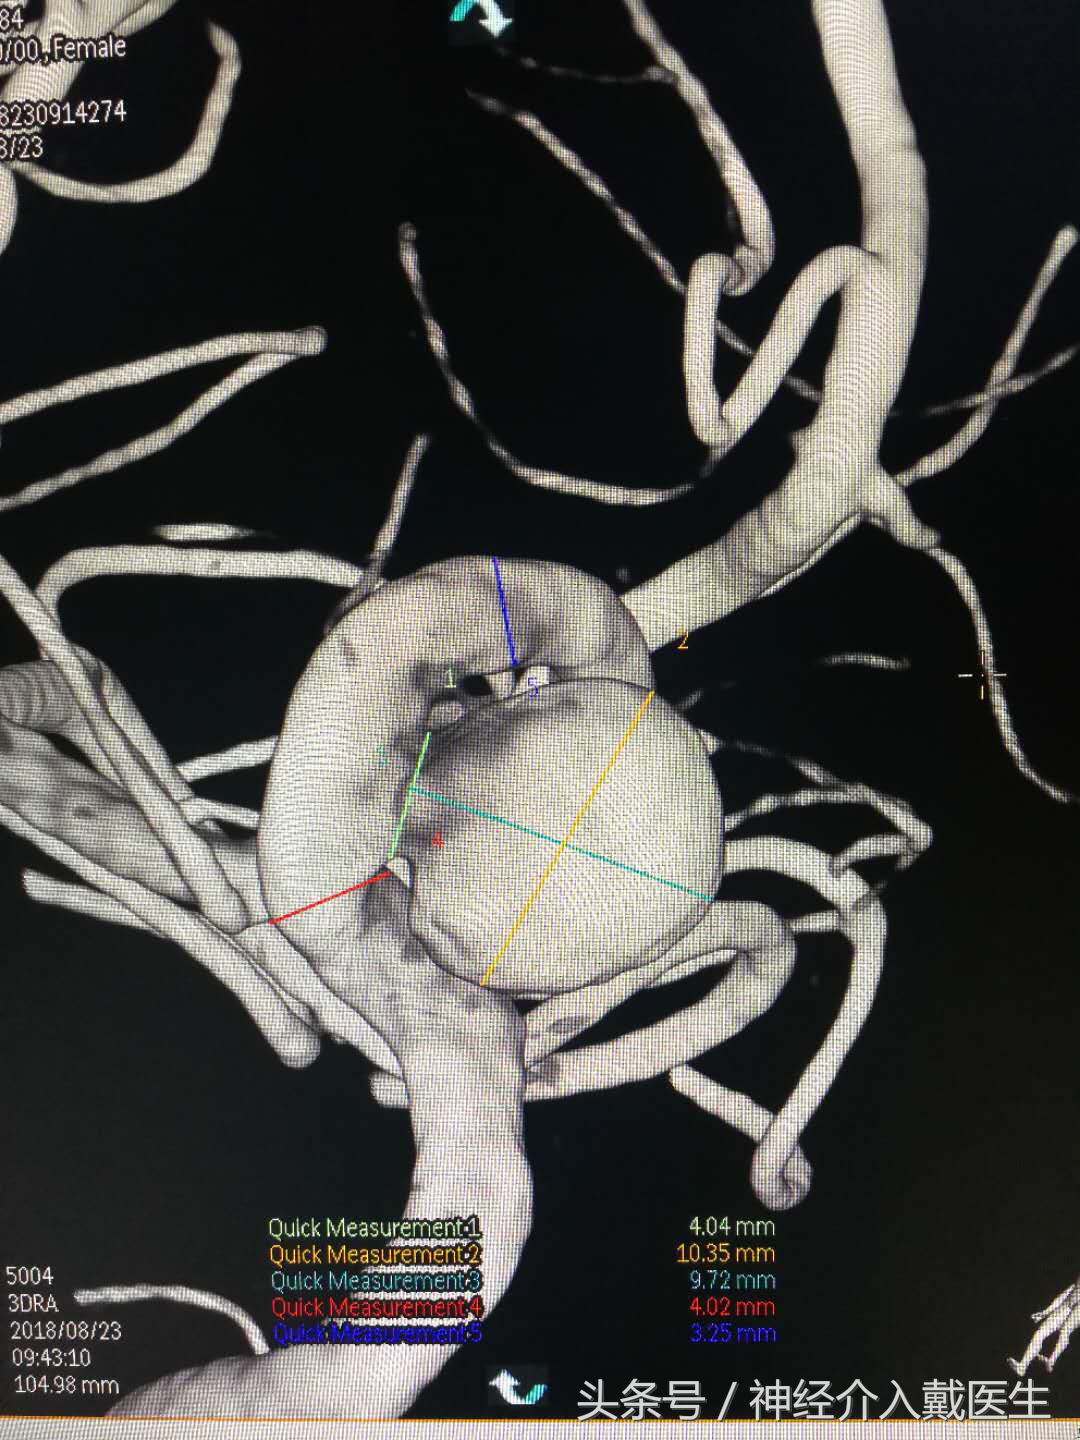

脑血管造影进一步明确右侧颈内动脉海绵窦大型动脉瘤,直径超过10mm,

3D图像显示瘤体,瘤颈,载瘤动脉关系,长度。